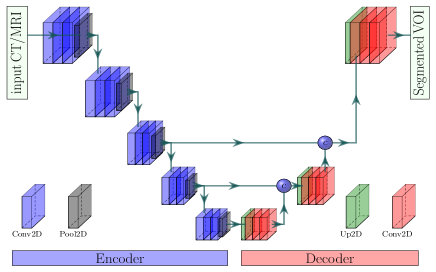

Segmentation of medical image has attained enormous progress notably since after the proposing of UNet [31]. Currently, CNN-based networks have been extensively practiced for the medical imaging domain, exceeding conventional image analysis techniques relying on hand-crafted features [53]. However, the CNN-based network for segmentation incorporates two fundamental elements: the encoder and the decoder [31]. An encoder consists of convolutional and pooling layers. The convolutional layers produce feature maps, whereas the pooling layers continuously decrease these feature maps’ dimension to gain more critical features with more eminent spatial invariance [17]. The decreased resolution feature maps also enlarge the maps’ field-of-view and diminish the computational expense [54]. The decoder projects the distinctive lower resolution features discovered by the encoder onto the higher resolution pixel space to achieve a compact pixel-wise labeling [55]. However, the simple encoder-decoder network, named EDNet, in our implementation is depicted in Fig 4.

However, the decreased feature maps due to pooling undergo spatial knowledge elimination injecting roughness, poor border knowledge, checkerboard artifacts, over-, and under-segmentation in the segmented substructures [17, 54, 31, 59]. To overcome these problems, the authors in [31] introduced skip connections in a UNet, permitting the decoder to retrieve the associated features discovered at all encoder steps that were missed due to subsampling in the encoder. The feature maps from the encoder’s antecedent layers are concatenated with the decoder’s identical scale through the appliance of skip connections. Applying the skip connection of the popular UNet, we propose a VGG-UNet, where we have also employed the VGG-16 network as an encoder, as shown in Fig. 5.

In our VGG-UNet, we apply the skip connections holding ladder-like compositions [60] motivated by UNet to succeed in the pooling weaknesses. All pooled layers of our network are concatenated channel-wise to a deconvoluted feature map with identical dimensions, where it acts as an offsetting link for the spatial knowledge dropped due to subsampling in the encoder.

Again, the authors in [54] combined features at varied coarseness levels of the encoder in their popular FCN to polish the output segmented VOIs. In this article, we propose a VGG-FCN, as shown in Fig. 6, with the pre-trained VGG-16 network in the encoder. The output feature map of such an encoder has -times fewer resolutions as VGG-16 has five pooling layers.

The employment of upsampling can output the segmented mask with the same size as the input image, called FCN32s. Such an upsampling produces a coarse or rough mask as it utilizes only global information from the more in-depth high-level features. The in-depth features are achieved while operating deeper, which causes the spatial location information lost. That indicates that output from shallower layers has more location knowledge. If we combine both local and global information, it can enhance the segmentation result. The output from the fifth pooling of VGG-16 is upsampled and fused with the fourth pooling in our network. Then, the combined map is upsampled and again linked with third pooling. Finally, we perform upsampling, which provides a segmented WHS mask. Hence, the proposed VGG-FCN is also named VGG-FCN8s, where we use both the local and global information to obtain the final mask.